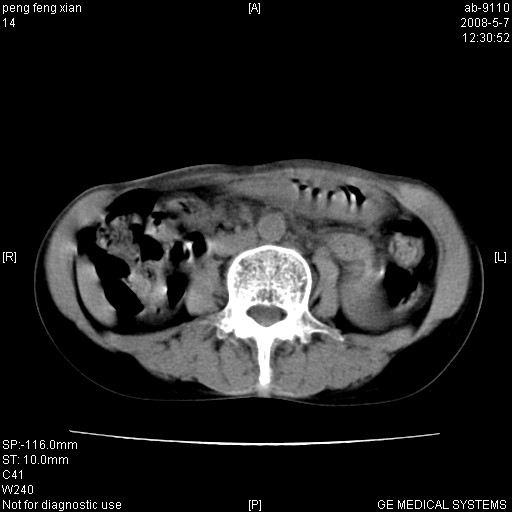

女,56岁。b超左一腹包块,考虑胃肠道肿瘤。

胃体部胃壁增厚,不均匀性强化,与胰腺分解欠情.

考虑:胃癌,胰腺受侵待除外.

鉴别:胃淋巴瘤(强化不明显)

建议:胃镜检查.

典型胃癌胰体尾部受侵。

胃壁增厚,左前胸壁局限性隆起,考虑胃癌可能性大,建议做胃镜

胃壁不规则增厚,考虑胃癌.应该多喝点水的.